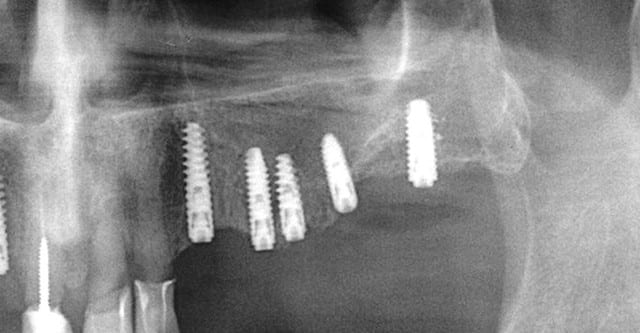

ce n'est pas fait dans l'ordre logique mais après la mandibule, le maxillaire... 12 à cassée (le patient pose sa prothèse pour dormir) donc je ne garde que 11/21/22 et pose d'implants.

Certains vont dire que je ne suis pas économique, mais le all on four ce n'est pas mon truc.

ouarf, mdr, l'implant en 47 est lingualé et tous les autres à partir du secteur antérieur partent sur la droite...comme pour tous les droitiers....

A ce sujet, plutôt que de looker l'axe de 47, jette un œil sur 26 .... il ne s'agit pas de montrer que je suis le meilleur, mais que des techniques simples et bien raisonnées permettent d'obtenir des résultats corrects et reproductible, et ce par n'importe quel dentiste consciencieux.

pour 26 (comme pour les 17 autres implants de ce cas) flapless intégral (même pas de puch), foret initial directement à travers la gencive) et uniquement des éponges de Gelatemp là où c'était nécessaire.

Donc coût très réduit, ce qui pourrait permettre de réduire au maximum le devis des implants....mais en réalité ça me permet surtout d'augmenter ma marge et de travailler moins pour le même résultat en fin d'année...:-))